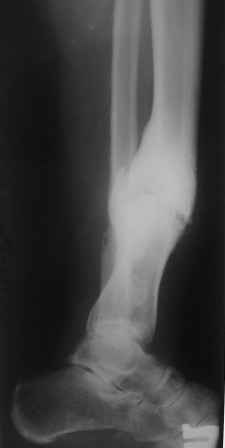

Больной 33г, лечится в течение 2-х лет, выходил на работу. Первоначально, был выполнен остеосинтез двумя шурупами с дополнительной фиксацией перелома наружной гипсовой повязкой. Снята преждевременно в поликлинике, через 3 месяца после операции, постепенно возникла варусно-рекурвационная деформация.Больному был наложен АВФ, с постепенной устранением деформации. Демонтаж АВФ через 4 месяца. Спустя 3 месяца появилась болезненность и стала нарастать деформация. В настояще время больной ходит с тростью, с полной нагрузкой на конечность. Имеется варусно-рекурвационная деформация 45-20 градусов. Болезненность при пальпации, незначительная подвижность в зоне перелома. Взгляды коллег разошлись: 1. Наложить АВФ с остеотомией м/б кости, постепенное исправление деформации, после, БИОС. 2.Наложение АВФ с остеотомией в зоне ложного сустава, коррекция деформации- постепенная, после исправления осей- БИОС. 3.Открытая репозиция перелома, одномоментное устранение деформации, БИОС.